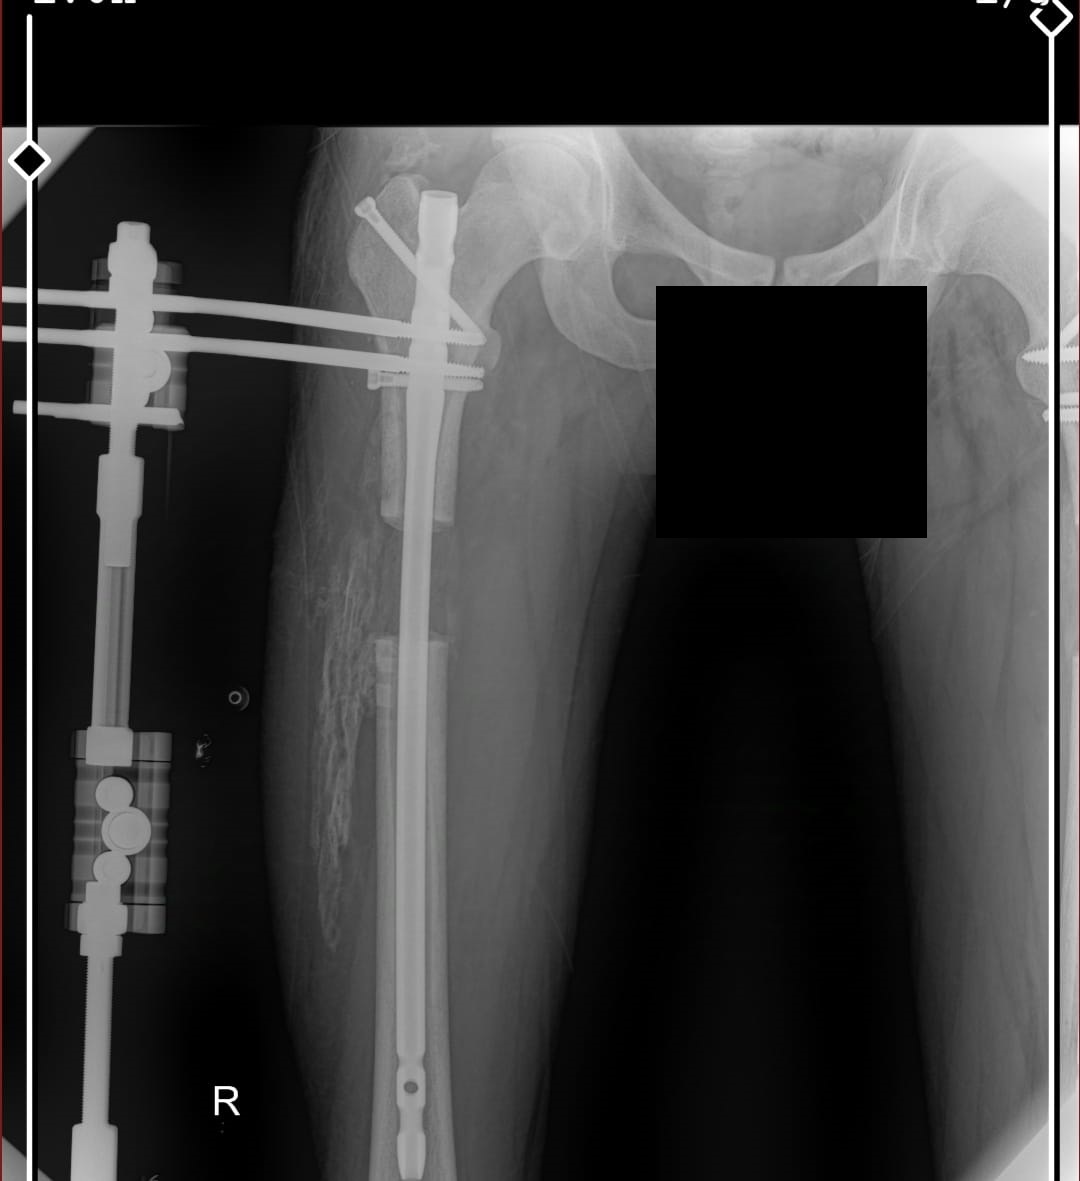

these are my xrays chronologically00 -

these are just before removing external fixatorAttachments: